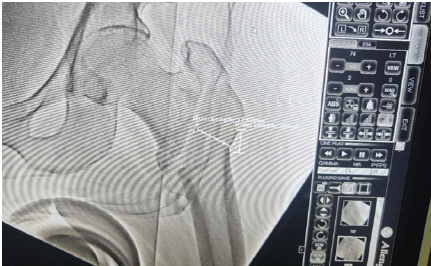

Integrity of the lateral wall is important in the management of intertrochanteric fractures, as about 21% of intertrochanteric fractures following fixation have post-operative lateral wall fracture [15], and among those, 22% undergo reoperation, with the remainder having protracted healing time or shortening in limbs [16,17]. Lateral wall integrity is also important for providing lateral buttress support and preventing varus collapse. The lateral wall thickness is defined as the distance in mm from a reference point 3 cm below the innominate tubercle of the greater trochanter, angled at 135° upward to the fracture line (the midline between the two cortex lines) on anteroposterior radiograph [18] .Lateral wall thickness is a simple and quantitative parameter for the pre-evaluation of the integrity of the lateral wall. Lateral wall integrity was also assessed in the immediate post-operative X-rays to see if it was maintained or lost post-fixation. (Fig.5)

Figure 5: Lateral wall integrity is seen on the fluoroscopic image.